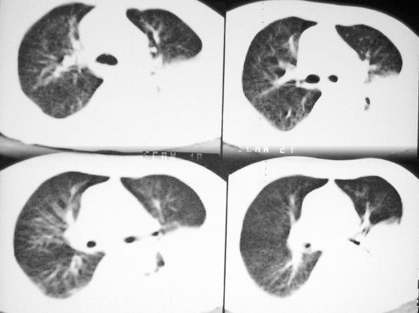

长年偏瘫卧床的病人,73岁,男。最近不能自理,饮食差,知觉不敏感,bp:140/80。脑ct是脑动脉硬化的表现,陈旧多发脑梗死。听诊左肺呼吸音低。行胸部ct扫描发现左侧大量胸腔积液,左侧肋骨虫蚀样破坏,请给予会诊一下:是否转移性病变还是其他?谢谢!

我认为长期卧床病人,其肋骨骨质稀疏,其左后肋骨之异常,多为陈旧骨折所致,

窗宽窗位未调好,有否骨质破坏很难定。

左侧后肋骨及椎弓骨质破坏,考虑转移瘤.降主动脉旁见一软组织块影,肿瘤与压迫之不张肺组织不能鉴别,建议增强扫描.

我建议化验胸水.肋骨破坏不像。

支持2楼战友的考虑。如果是转移的话,周围软组织也应该受浸润,而现有图片显示双侧软组织比较对称。恶性征象不足,加上病史长年偏瘫卧床的病人,73岁,男。最近不能自理,饮食差,知觉不敏感,bp:140/80。可能有陈旧性骨折,病人感觉迟钝而被忽略。

我认为长期卧床病人,其肋骨骨质稀疏,其左后肋骨之异常,多为陈旧骨折所致,是否转移证据不足,如有原发灶,也可以考虑一下,

感觉不象破坏,建议楼主不妨拍cr胸片.

感觉不象肋骨破坏。

左侧胸水 肋骨破坏不象

考虑;左侧周围性肺癌侵犯胸膜并肋骨转移.

考虑肋骨骨质破坏,病变肋骨皮质不连续,呈融骨样改变,不象骨质损伤后的修复样改变,未见到明显骨痂显示.软组织肿胀不明显,所以不太支持感染性破坏改变.

肋骨骨质破坏!!中下部纵隔窗传上来看看!该不会有肺癌吧?纵隔内有淋巴结影。

左肺上叶尖后段实变、体积缩小,支气管开口后方似有一肿块,与胸壁、主动脉分界不清,局部肋骨呈混合型破坏,考虑肺癌肋骨、胸膜转移。

同意四楼意见!左侧椎板也有骨质破坏征象

左侧包裹性胸腔积液,未见到明确的肿块影,纵隔窗伪影严重,纵隔可见到淋巴结(位于主动脉弓下)左侧肋骨病变是否与患者长年卧床有关